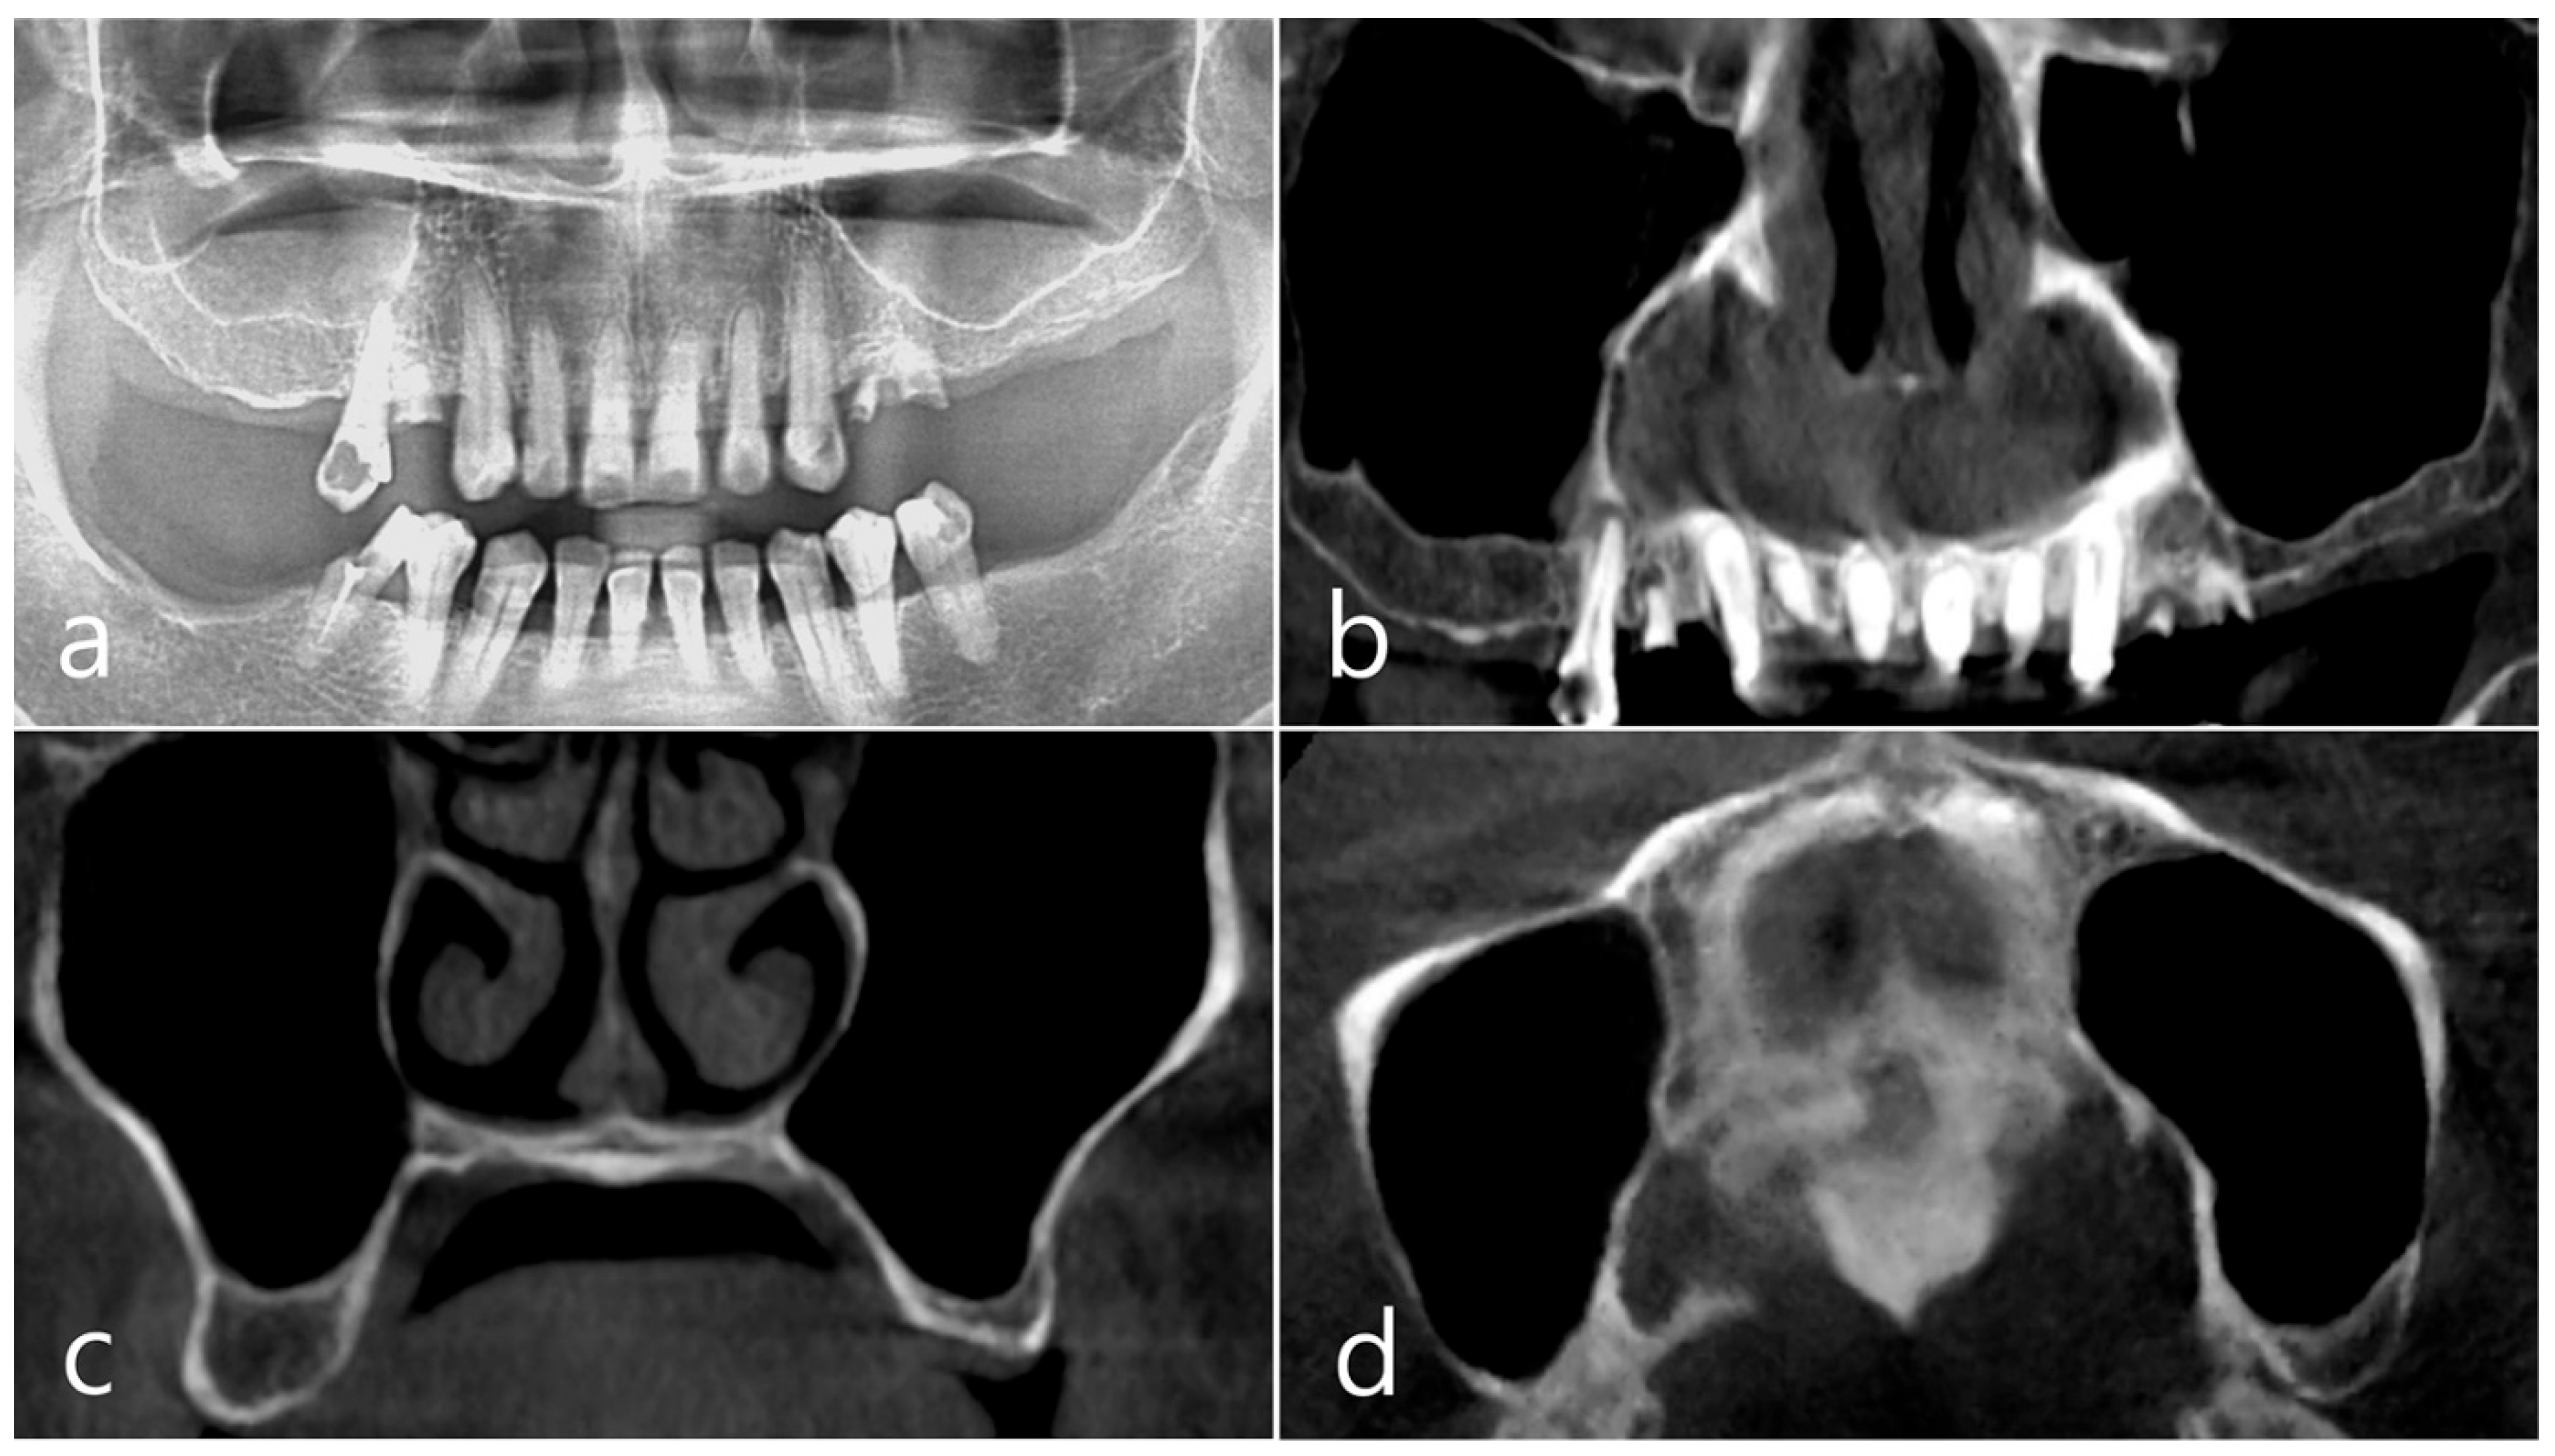

In the CBCT image taken immediately after the procedure, a well-filled bone graft substitute without perforation of the sinus membrane was observed (Figure 8d–f). However, extensive bone loss was found in CBCT images taken 2 years after the prosthesis was placed. The facial cortical bone plate was lost, and bone resorption was present only within the sinus graft. The appearance of the sinus graft was not invaded, and the thickness of the sinus mucosa was normal (Figure 8g–i).

Surgical intervention was decided after the prosthesis was retrieved (Figure 9a). Under local anesthesia, the buccal mucoperiosteal flap was reflected. A severe bone defect was observed in the sinus bone graft of the #26 implant. Thorough debridement was performed on the bone defect in the maxillary sinus bone graft. There was no difficulty in removing the inflammatory granulation tissue because it bordered the surrounding healthy bone graft (Figure 9b). The exposed implant achieved osseointegration, but the large implant surface was exposed and contaminated. Mechanical decontamination was thoroughly performed using a titanium brush and titanium curette, and additional detoxification with tetracycline HCl was performed (Figure 9c). After sufficient saline irrigation again, a bone graft (Osteon II, Genoss, Suwon, Republic of Korea) was performed (Figure 9d). The bone graft area was covered with a resorbable collagen membrane (Genoss, Suwon, Republic of Korea) (Figure 9e). The mucoperiosteal flap was closed with 4-0 nylon. Healing was uneventful, and the prosthesis was re-inserted again 1 month after GBR. The specimen was fixed in 10% formalin for histopathological examination. In the specimen, granulation tissue infiltrated with inflammatory cells, and necrotic bone graft particles were observed (Figure 9f). The patient was followed up once every 6 months, and panoramic radiography and CBCT were taken 2 years after GBR (Figure 10a,b). The bony defect was filled with bone tissue, and no abnormal radiographic images were observed. Corticalization of the buccal bone was well achieved (Figure 10c,d).

Figure 8. (a) Teeth #24 and #25 were extracted, midcrestal and vertical incisions were performed, and mucoperiosteal flaps were reflected; (b,c) A lateral sinus window was prepared, and sinus floor elevation was performed without membrane perforation. The bone graft substitute was delivered and covered with a resorbable collagen membrane. The flap was closed; (df) In the CBCT image taken immediately after the procedure, a well-filled bone graft substitute without displacement was observed; (gi) Extensive bone resorption around #26 implant was observed in CBCT images taken 2 years after prosthesis delivery. The buccal cortical bone plate was lost, and bone resorption was present only within the sinus graft.

Figure 10. (a,b) In panoramic radiography and CBCT images taken 2 years after GBR, the sinus graft site of the maxillary sinus was well filled with bone tissue, and no abnormal radiographic images were observed; (c,d) On coronal and axial images of CBCT, homogeneous findings were observed in the previous bone defect site. Corticalization of the facial bone plate was well achieved.